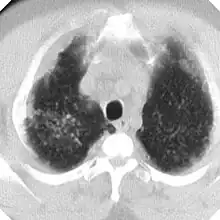

La silicosis complicada se caracteriza por la presencia en los pulmones de masas de diámetro superior a 1 centímetro llamadas masas de Fibrosis Masiva Progresiva (FMP) que al retraerse generan bullas en su periferia y distorsionan los bronquios determinando obstrucción y limitación del flujo aéreo, aparte de otras complicaciones (neumotórax, cavitación aséptica, cavitación por tuberculosis, etc). Si las masas alcanzan cierto tamaño alteran notablemente los parámetros de función pulmonar, tanto de ventilación como de intercambio de gases. Silicosis aguda, la cual resulta de la exposición a cantidades muy grandes de sílice durante corto tiempo. Los pulmones se inflaman bastante y se pueden llenar de líquido, lo que causa una dificultad respiratoria grave y una baja de los niveles de oxígeno en la sangre.

La silicosis complicada se caracteriza por la existencia de masas de Fibrosis Masiva Progresiva, también llamadas masa conglomeradas, con diámetro mayor de 1 cm. Es una enfermedad grave, sobre todo si las masas son de gran tamaño, y disminuye notablemente la esperanza de vida de los pacientes. La evolución de la forma simple a complicada se debe a factores muchas veces desconocidos. Entre los factores conocidos destacan: elevada exposición a sílice, abundante profusión nodular, tuberculosis y enfermedades del colágeno.

En caso de dudas diagnósticas se puede recurrir a la Tomografía Computada de Alta Resolución (TACAR) que se ha mostrado más sensible y específica para el diagnóstico.[9] Somete al paciente a mucha más radiación que la Rx y no debe usarse como prueba diagnóstica de primer nivel sino para aclarar dudas. La TACAR permite comprobar cómo las masas de FMP se originan frecuentemente en región subpleural de zonas apicales posteriores desplazándose progresivamente de la pleura —signo del desprendimiento—.[3]